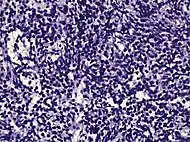

| Acinar adenocarcinoma - 93%[2] | Adenocarcinoma (not otherwise specified/ conventional/ usual acinar)[3] |

77%[notes 2] | 54%[notes 2] | ![]() |